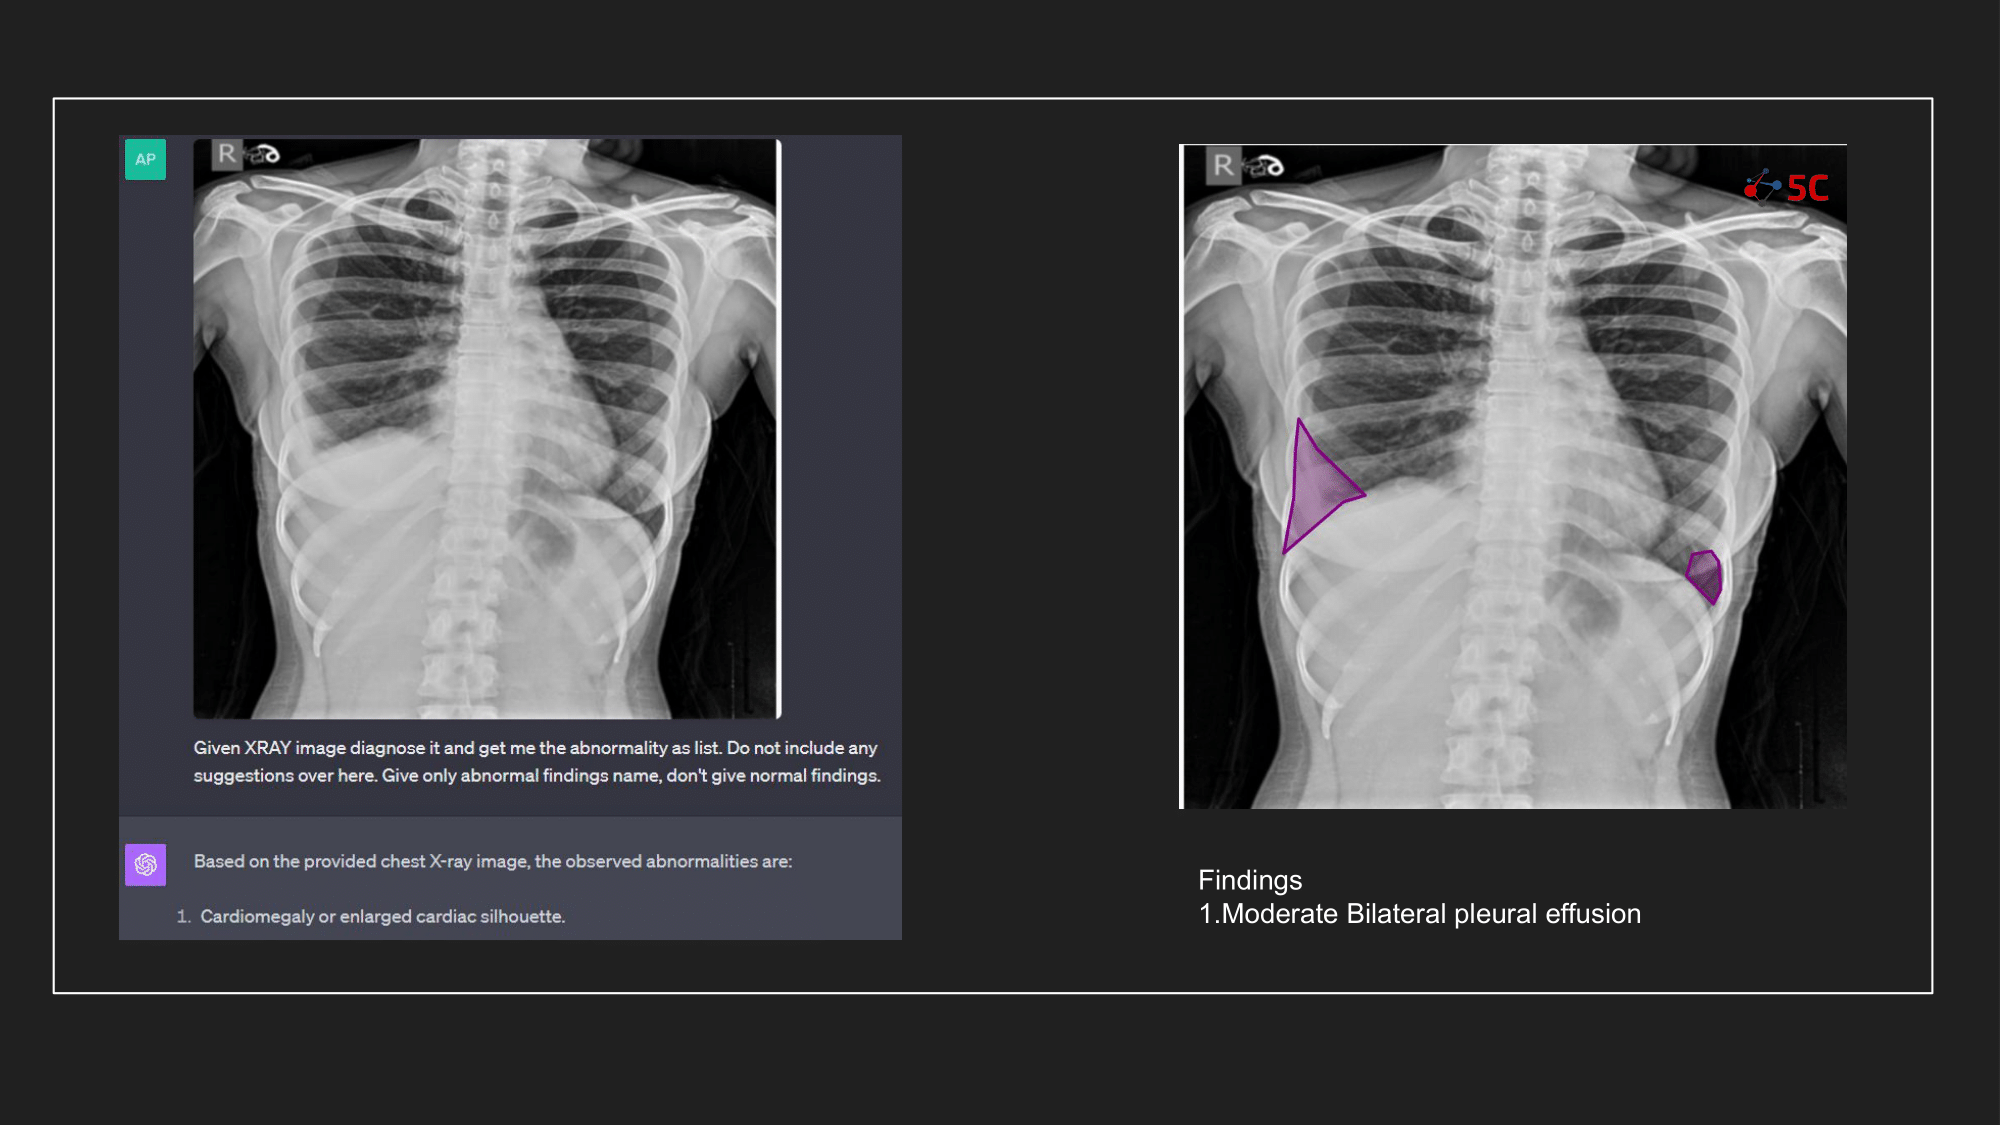

To gauge GPT-4V's prowess in detecting pleural effusion, an experiment was conducted with 10 random chest X-rays known to have pleural effusion. The XRays were sent to GPT-4V, Radiologists as well as to 5C's AI.

Presented below are the results from the experiment.

The output from GPT-4V and from 5C's AI model for the Chest XRays are provided at the end of the post.